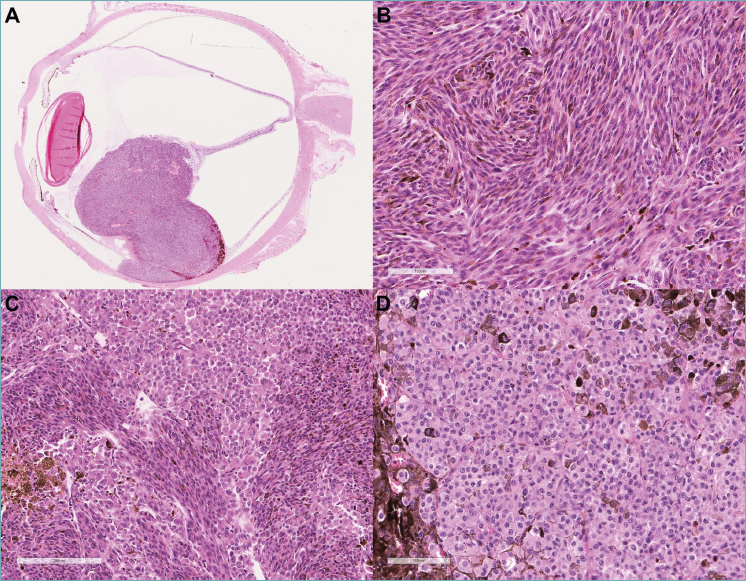

The study cohort included 84 patients, with 47 males (56%) and 37 females (44%). Age at diagnosis ranged from 20 to 95 years, with a median of 68 years and a mean of 66. Tumor localization was predominantly in the choroid (79 cases, 94%), followed by the ciliary body (4 cases, 5%) and the iris (1 case, 1%). Histologically, using a 90% cellularity cutoff, 46 tumors were classified as spindle-cell (55%), 13 as epithelioid (15%), and 25 as mixed (30%) (Fig. 1). Regarding staging, 7 tumors were classified as T2 (8%), 19 as T3 (23%), and 58 as T4 (69%). Follow-up data were available for 49 patients. The mean follow-up duration was 34.3 months, with a median of 24.5 months (range: 1.3–122.3 months). Metastatic dissemination was observed in 11 cases (22%) of evaluable patients, and 6 patients (12%) died due to disease progression.

Figure 1. Panoramic view of a choroid-based uveal melanoma (A, original magnification ×10, hematoxylin and eosin stain). Spindle-cell uveal melanoma (B, original magnification ×100, hematoxylin and eosin stain). Mixed-cell uveal melanoma (C, original magnification ×100, hematoxylin and eosin stain). Epithelioid-cell uveal melanoma (D, original magnification ×100, hematoxylin and eosin stain).